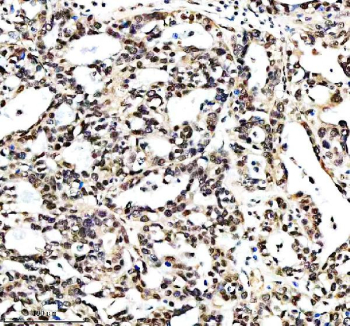

Immunohistochemical staining of RTRAF using anti-RTRAF antibody. RTRAF was detected in a paraffin-embedded section of human lung cancer tissue. Heat mediated antigen retrieval was performed in EDTA buffer (pH 8.0, epitope retrieval solution). The tissue section was blocked with 10% goat serum. The tissue section was then incubated with 2 ug/ml rabbit anti-RTRAF antibody overnight at 4oC. Peroxidase Conjugated Goat Anti-rabbit IgG was used as secondary antibody and incubated for 30 minutes at 37oC. The tissue section was developed using an HRP secondary and DAB substrate.